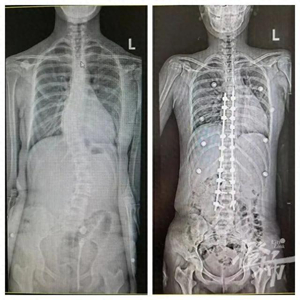

可可手术前后的对比图。